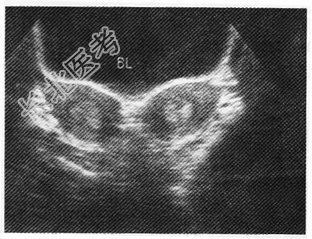

- 单项选择题女性,26岁, 婚前体检,超声检查如图所示, 最可能的诊断是

D、双子宫

E、双角子宫